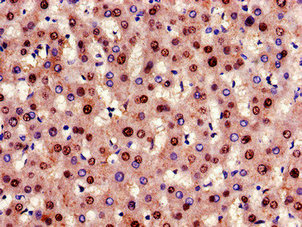

適用于WB、IHC、IP、FC等多種實驗技術,滿足您不同的研究需求。

| BCL2 Recombinant Monoclonal Antibody | CSB-RA564360A0HU | BCL2 | Human, Mouse | ELISA, WB, IHC |

| BCL2 Recombinant Monoclonal Antibody | CSB-RA002611A0HU | BCL2 | Human, Mouse, Rat | ELISA, WB, IHC, FC |